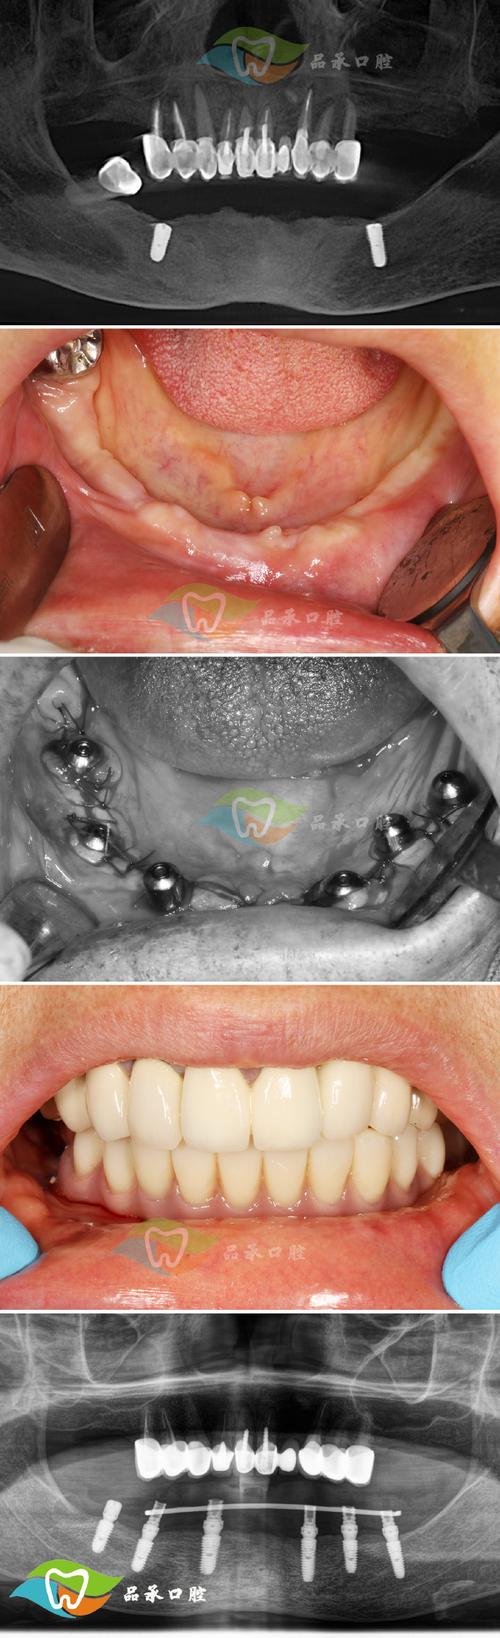

- 影像学: 全口曲面断层片(评估牙根位置、骨量)、CBCT(关键! 精确评估植入区骨量、牙根位置、神经血管位置,选择最佳植入点和角度)。

- 拍片确认位置(曲面断层或CBCT)。